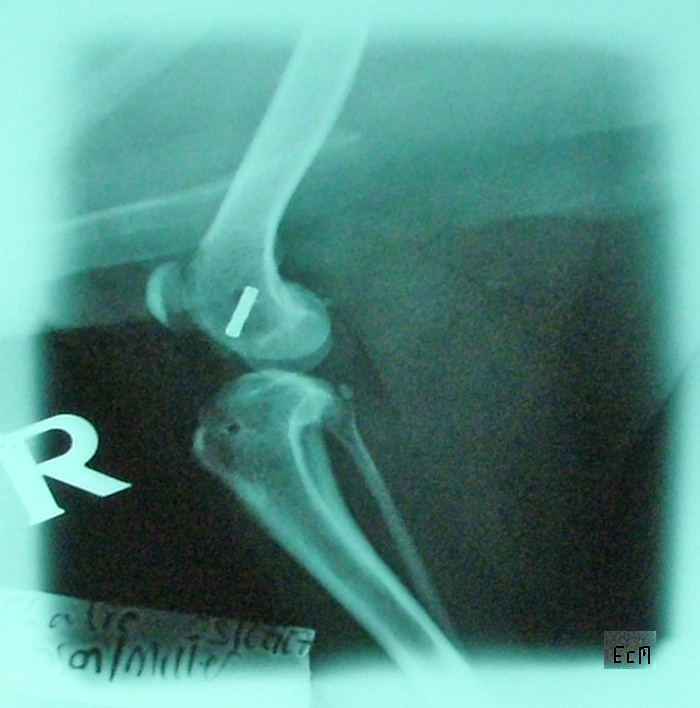

X-ray images of Charlie's leg. 2007